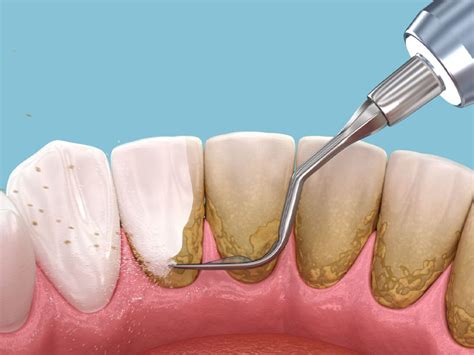

Una limpieza dental profunda, también conocida como "raspado y alisado radicular", es un tratamiento que va más allá de la limpieza dental regular.

¿En Qué Consiste?

- Raspado: Eliminación de placa y sarro tanto en la superficie de los dientes como debajo de las encías.

- Alisado radicular: Suavizado de las superficies de las raíces de los dientes para prevenir la acumulación de bacterias.